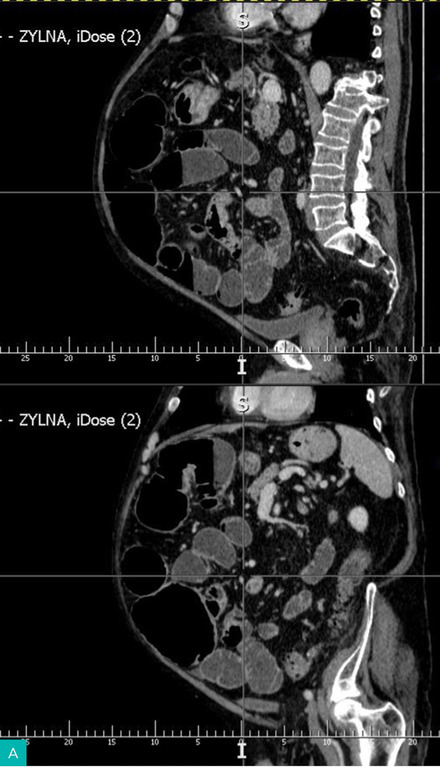

Diagnostyka: Wykonuje się przeglądowe zdjęcie RTG jamy brzusznej w celu potwierdzenia niedrożności (ryc. 1 i 2) i/lub tomografię komputerową (TK) ujawniającą rozdęte pętle jelit powyżej guza (ryc. 3).